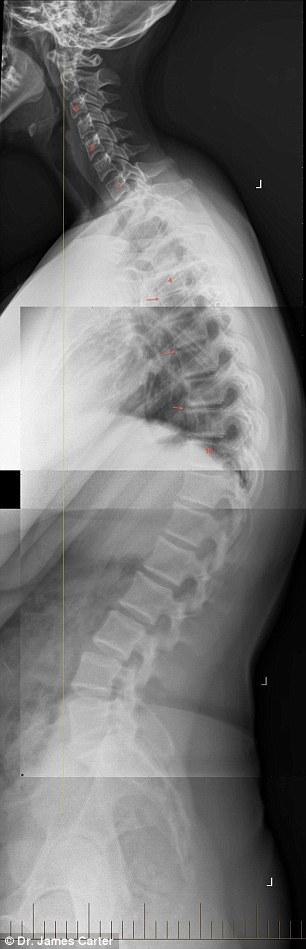

Pentru a atrage atenţia şi mai mult asupra acestei boli, un doctor din Australia, James Carter, a dat publicităţii mai multe radiografii şocante cu coloanele vertebrale ale unor tineri, inclusiv a unei fete de 16 ani care dezvoltă cocoaşă.

Boala a fost descoperită de specialiştii americani care au botezat-o „text-neck“. Practic, de la faptul că stau aplecaţi foarte mult deasupra smartphonurilor, a tabletelor sau a laptopurilor copiii, tinerii dezvoltă o cocoaşă care poate duce la afecţiuni grave ale coloanei. Americanii spun că boala nu trebuie neglijată şi chiar au decis să înfiinţeze un institut unde să se cerceteze în amănunt cât de afectată poate fi coloana vertebrală de folosirea în exces a noilor tehnologii. Cocoaşa apare în partea de jos a gâtului chiar între umeri.